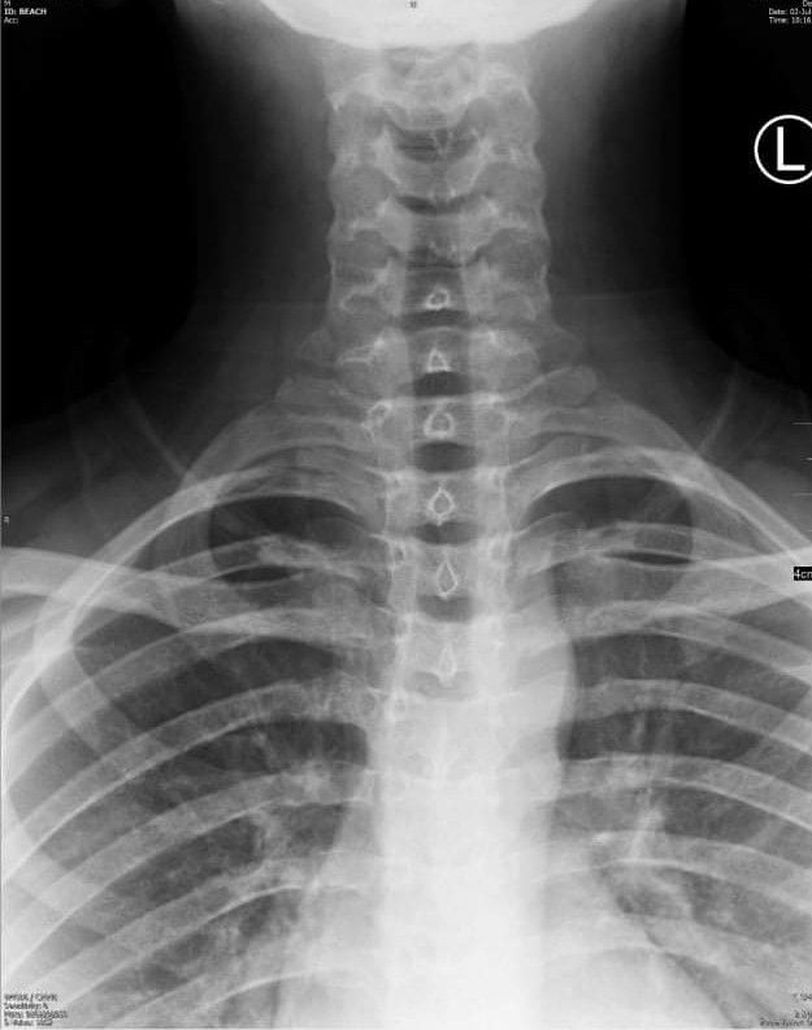

What is diagnosis

Male Patient 17 years old

Cervical rib ?

Rib fracture?? 1st rib

Steeple sign?